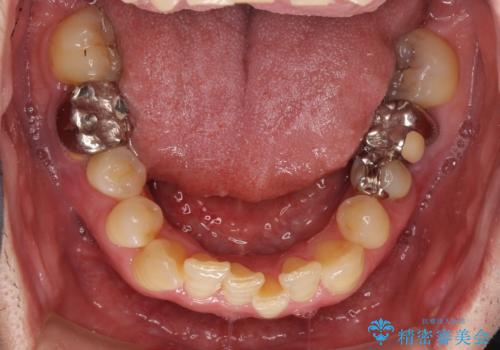

左右下顎の大臼歯は、ともに歯根が破折しており、抜歯が必要な状態でした。

放置したことで炎症による骨吸収が顕著であるため、骨造成を併用してインプラント埋入を行うこととしました。

咬み合わせは受け口傾向であり、上顎前歯の叢生が顕著であったことから、第1小臼歯抜歯による矯正治療も検討しましたが、下顎大臼歯を左右ともに抜歯するため、非抜歯による矯正治療を行うこととしました。